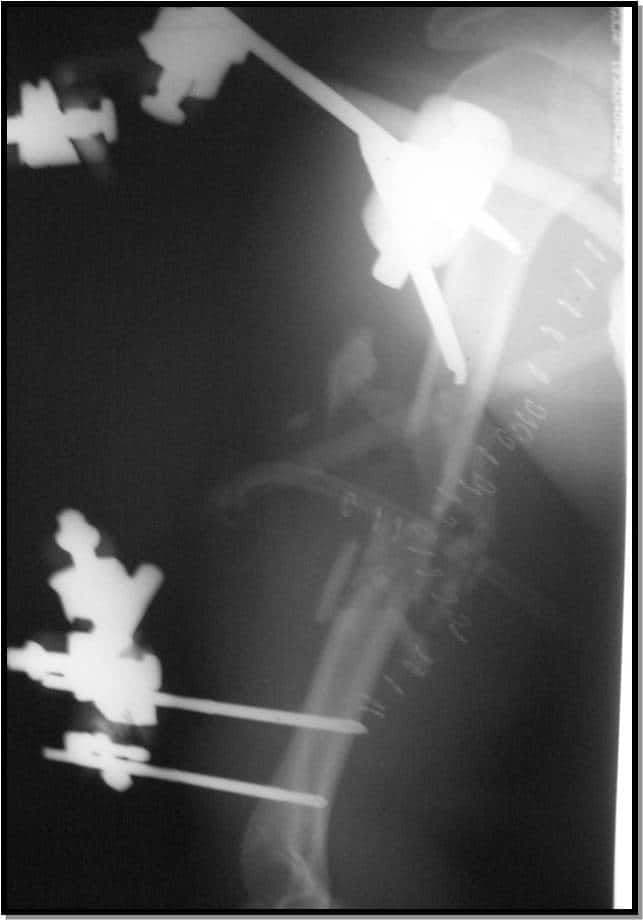

2. Уникайте встановлення штифта занадто близько до місця перелому (штифти всередині самого перелому зменшать здатність зовнішнього фіксатора підтримувати стабільність перелому) (зобр. 2 і зобр. 3. Рентгенологічний знімок цієї гомілки у прямій проекції передбачає адекватне розміщення зовнішнього фіксатора, проте на бічному знімку видно, що проксимальний штифт дистальної групи штифтів знаходиться всередині перелому).

Зобр. 2

Зобр. 3